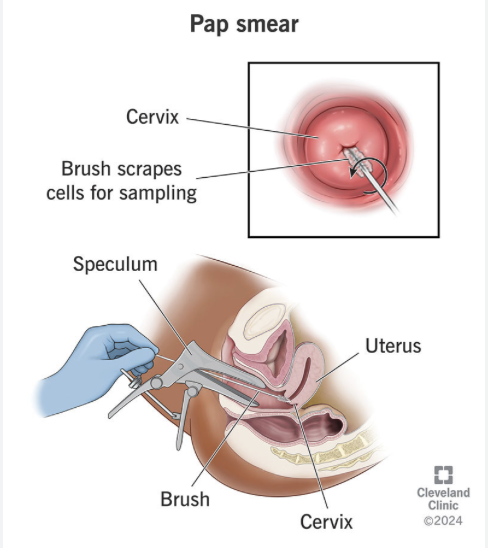

Pap

pananicolaou test

Also known as a Pap smear

Diagnostic Test